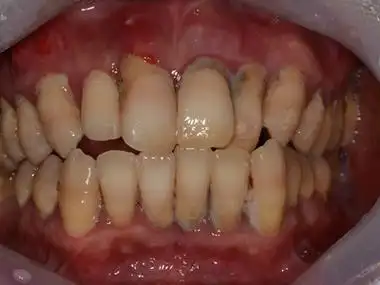

上下门牙牙龈红肿出血半年多求怎么治疗有实拍图片

往右第二个和第三个有太严重的牙龈萎缩,牙龈发炎红肿的很厉害,牙结石